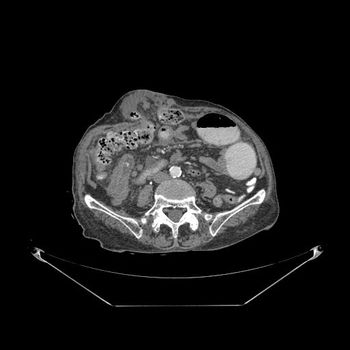

A 55-year-old woman presented to the surgical emergency unit with symptoms of acute intestinal obstruction for the last three days and worsening over the last 24 hours.